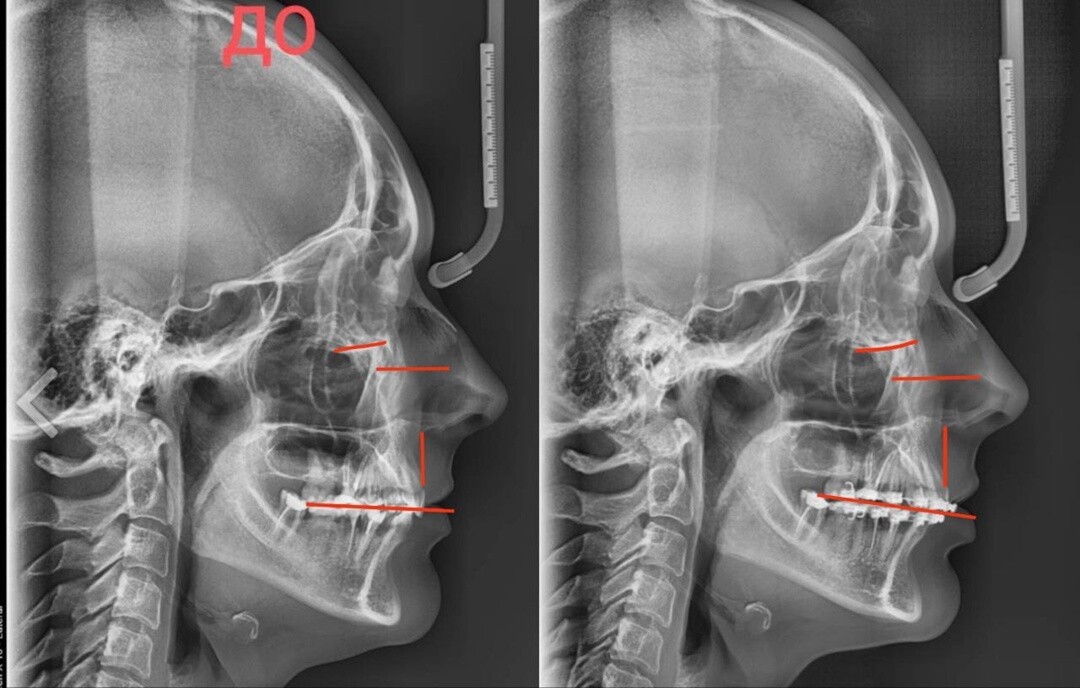

Но интересно другое. Там есть снимки черепа и можно сравнить. Листай карусель👇

Отметила на них самое очевидное.

И хотя такие исследования надо делать в программе и по КТ, но даже так несколько моментов видны невооруженным глазом.

Вот все эти расстояния, отмеченные красным - увеличились, и изменился наклон окклюзионной плоскости. И шея пошла вперед.

Плюс из-за отсутствия жевания на брекетах уходят объемы с жевательных мышц, что добавляет скелетизацию.